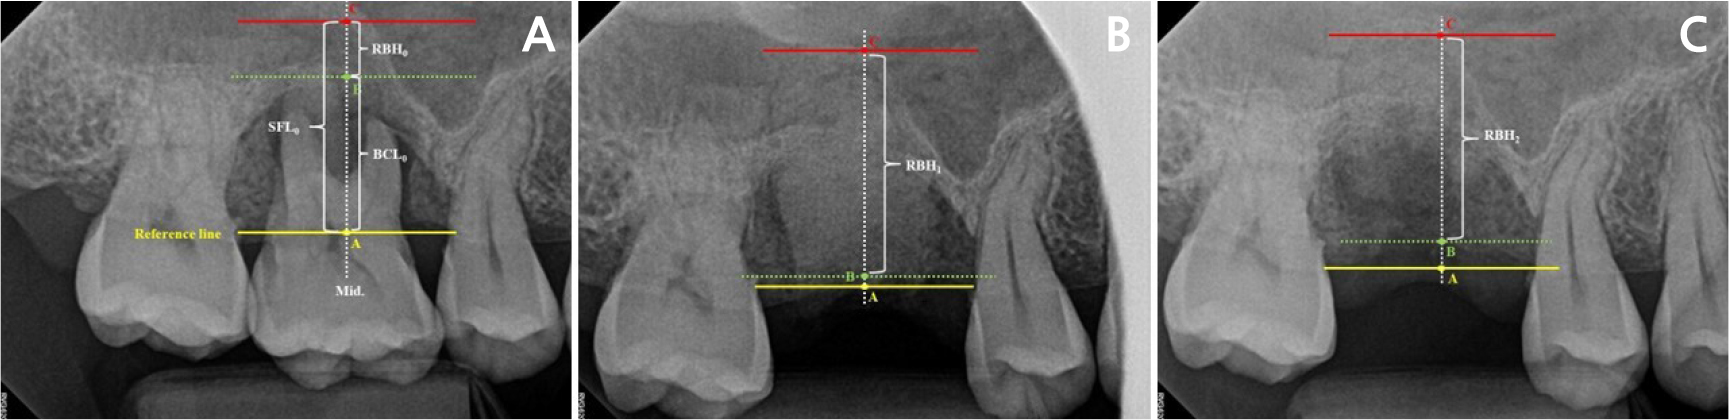

The following parameters were measured as described in the study by Jung et al.15 (Fig. 3):

(1) Sinus floor level (SFL): vertical distance between the reference line and the sinus floor at the center of the extraction socket.

(2) Bone crest level (BCL): vertical distance between the reference line and the crestal bone at the center of the extraction socket.

(3) Residual alveolar bone height (RBH): vertical distance between the sinus floor and bone crest.

(4) ΔSFL, ΔBCL, and ΔRBH: changes in SFL, BCL, and RBH between T0 and T2.

The ΔSFL represents the amount of sinus pneumatization, and ΔBCL indicates crestal bone shrinkage, and ΔRBH reflects bone gain.

Fig. 3

Radiographic measurements. For vertical measurements, the reference line (yellow) was defined as the extended line of the crest levels on each side, and the midline (middle, white dotted) was defined as the line passing through the center-most area of the extraction socket. A (yellow), B (green), and C (red) represent the contact points formed by the reference line and midline. SFL and BCL were measured from A to C and A to B, respectively. RBH was measured from B to C. Yellow A, green B, and red C represent the RBHs at T0, T1, and T2, respectively (RBH0, RBH1, and RBH2). T0: before extraction; T1: immediately after extraction and ARP; T2: shortly before implant placement.